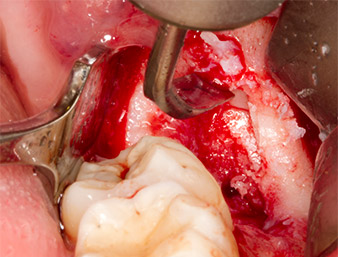

Le tissu recouvrant le reste radiculaire n’est pas entièrement ossifié et est essentiellement constitué de tissu de granulation modifié par l'inflammation (Fig. 4).

Tissu de granulation

Fig. 4 : Deux écarteurs Lagenbeck et un raspatoire exposent la zone d’intervention. On aperçoit le tissu de granulation de la première ostéotomie non totalement cicatrisée.

Pour exposer le reste radiculaire en minimisant le traumatisme causé aux tissus, un autre insert est utilisé (Piezomed S2) qui est principalement indiqué pour la préparation de la fenêtre latérale dans les élévations de plancher sinusien. La boule diamantée est également utilisée pour adoucir les bords osseux tranchants (Fig. 6 et 7). Tous les inserts Piezomed sont utilisés avec le paramétrage par défaut automatique, et sans la fonction Booster.

Piezomed S2

Fig. 6 : Le reste radiculaire est soigneusement exposé à l’aide d’un insert sphérique diamanté (Piezomed S2), les arêtes osseuses sont adoucies.

Reste radiculaire 38

Fig. 7 : Le reste radiculaire 38 (LL8) est bien exposé dans son alvéole en vue de son extraction ultérieure.